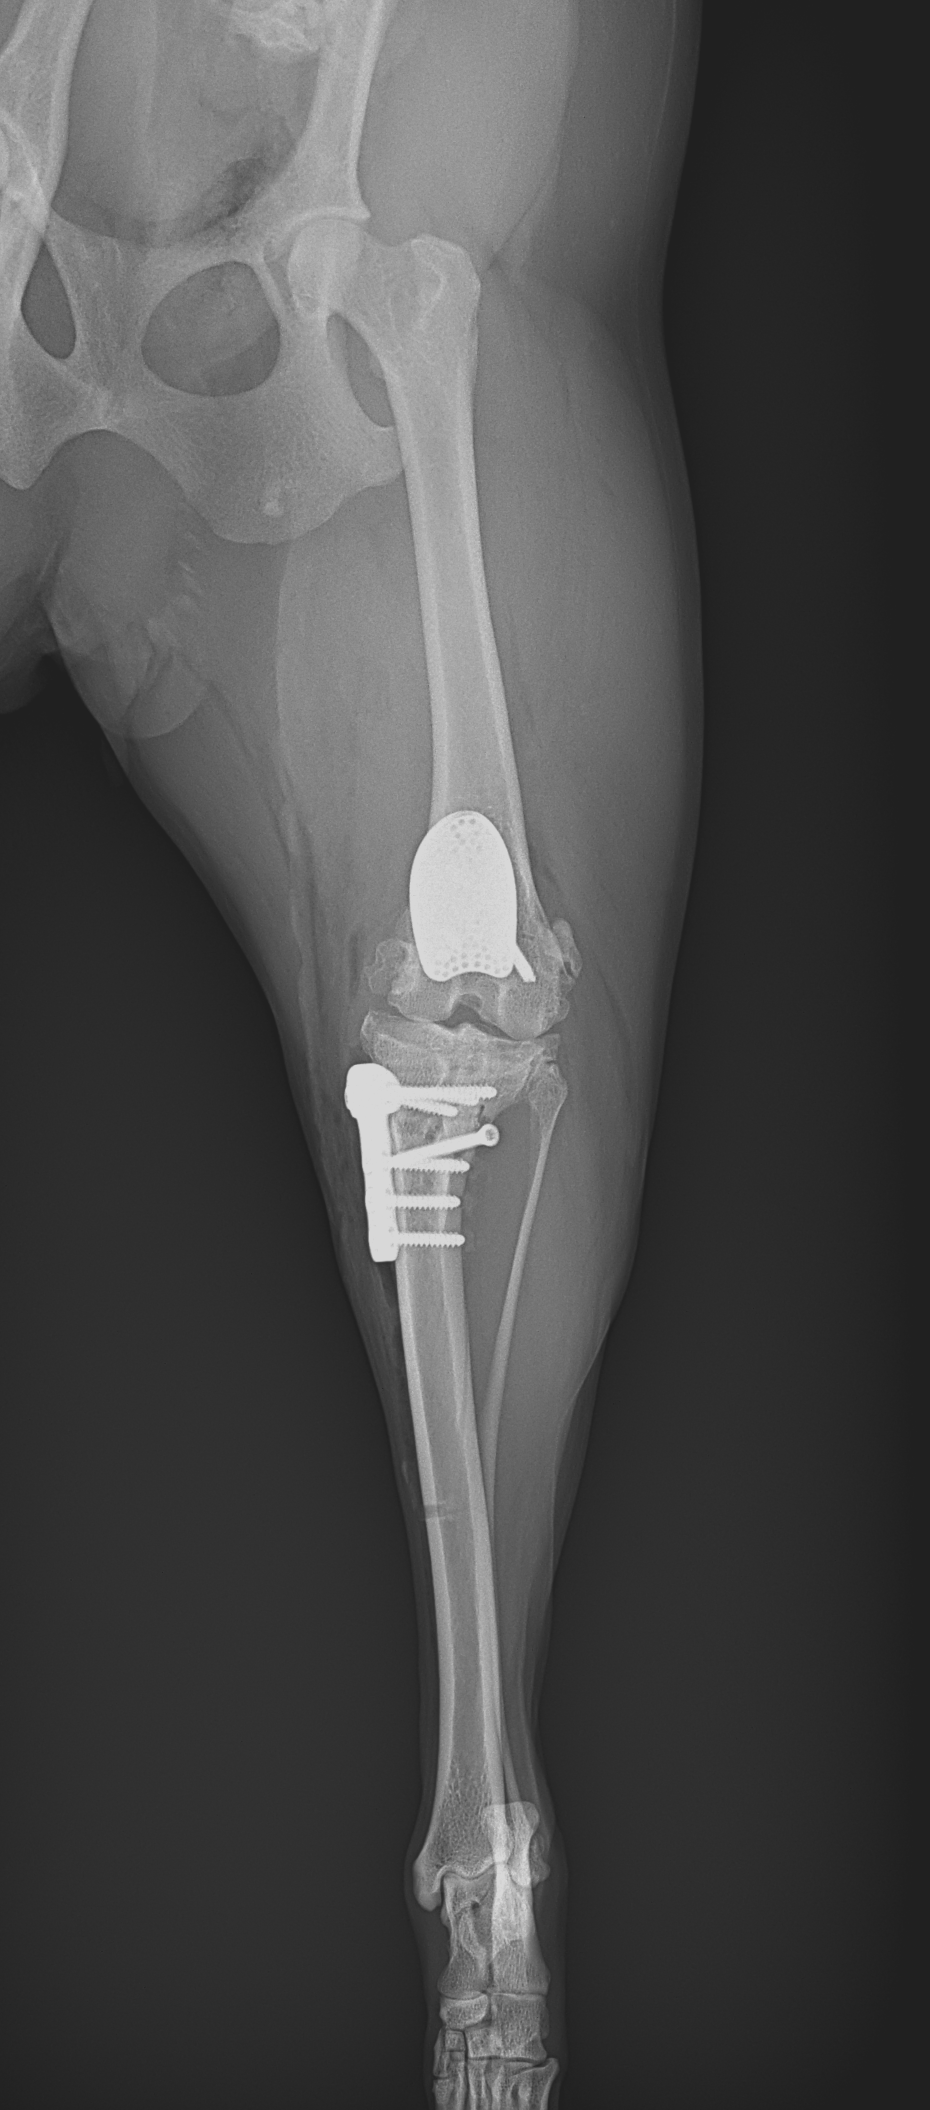

膝蓋骨内方脱臼+前十字靭帯断裂 PGR#21+CBLO #251

過去に膝蓋骨内方脱臼G4で手術を受けている患者さんが、急に跛行を呈するようになったとの事。関節炎が顕著であり、前十字靭帯断裂の併発も疑われます。ファットパッドサイン陽性、脛骨圧迫試験陽性、脛骨ピボット圧迫試験陰性でした。大腿骨滑車のリプレイスメントとCBLOで対応しました。